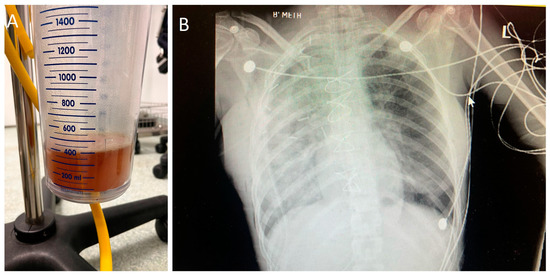

Large Intrathoracic Desmoid Tumor and Re-Expansion Pulmonary Edema: Case Report and Review of the Literature

2. Case Report